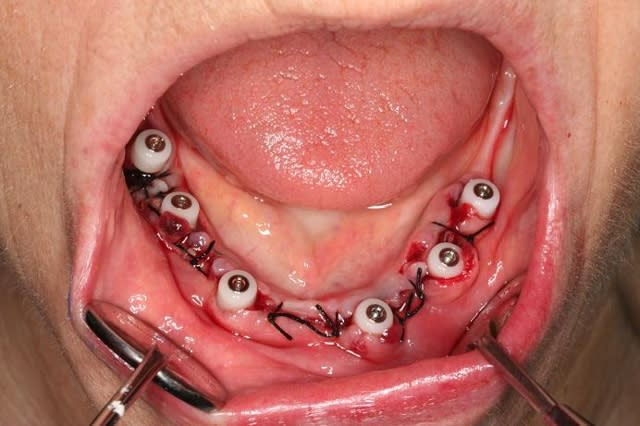

voici un cas extraction, implantation immédiate, mise en charge à 1 jour.

photo1:cas initial paro, mais os résiduel d'un bon volume.

photo3:extractions et curetage alvéolaire++++++

photo 4:pose de 6 implants evl compacts 4/12 (serf). Tous à plus de 45N, sauf en 36...

photo 5: le lendemain, transvissé pret ( on evite 36, pour le laisser tranquille)

photo 6: aspect à 1 jour.

photo 7: transvissé, vissé!

ce fut une grosse matinée, car le curetage fut long et minutieux, ainsi que le modelage des rebords alvéolaires...